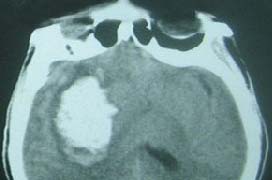

腦出血,俗稱腦溢血,屬于“腦中風”的一種,是中老年高血壓患者一種常見的嚴重腦部并發(fā)癥,是指非外傷性腦實質內血管破裂引起的出血,常見的病因是高血壓、腦動脈硬化、顱內血管畸形等,常因用力、情緒激動等因素誘發(fā),故大多在活動中突然發(fā)病,臨床上腦出血發(fā)病十分迅速,主要表現為意識障礙、肢體偏癱、失語等神經系統(tǒng)的損害。目前世界逐漸步入老齡化,腦出血已成為一較為廣泛發(fā)生的急癥重癥,我國每年因為腦出血死亡的患者約占全部疾病死亡的20%左右,嚴重威脅人們的健康。

治療腦出血主要采用定向軟通道技術和顱內血腫微創(chuàng)清除術,效果令人滿意;颊呔唧w選擇哪種療法,需要結合患者病情和臨床醫(yī)師的診斷。